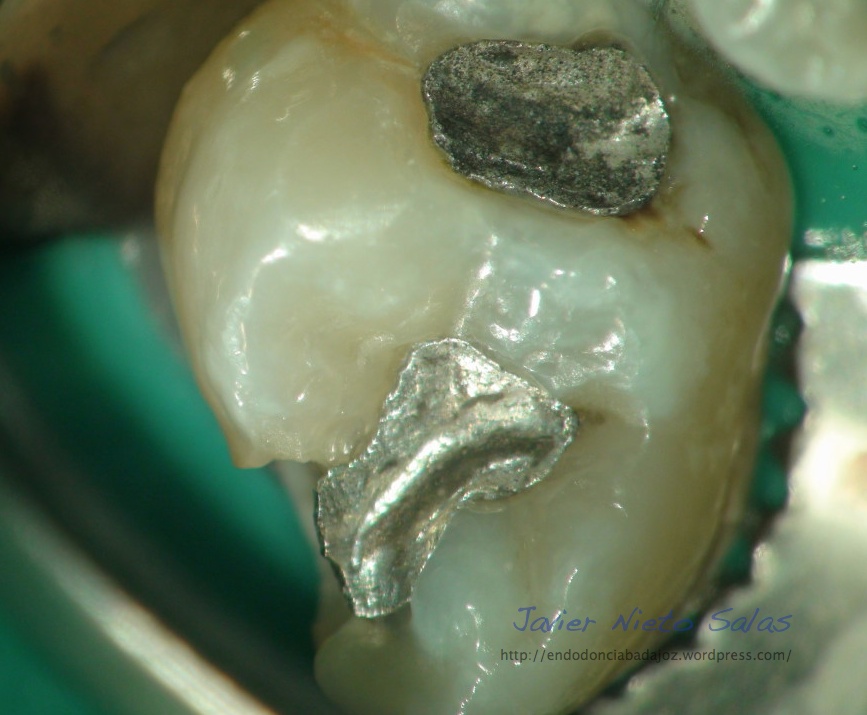

Una de sus muchas ventajas, las cuales no voy a entrar a describir ahora, es la facilidad de poder conservar en la fase de apertura el tejido remanente de la corona, no es necesario realizar una apertura deficiente para que sea conservadora, gracias a la magnificación y la luz coaxial, podemos tallar la cámara pulpar lo justo y necesario para localizar y preparar los conductos sin necesidad de hacer una gran apertura, necesaria para poder trabajar sin esta opción.

El caso de hoy, se trata de ver esta ventaja que podemos ofrecer en algunos casos a nuestros pacientes, no en todos, por que la disposición de los conductos y la caries , nos van a condicionar.No quisiera destacar tanto el tratamiento en sí, y darle más importancia a la apertura, fase muy importante, capaz de hacer, en muchas ocasiones que una endodoncia se complique o sea más sencilla.

Vamos a colocar una serie de fotos de diferentes aperturas e intentaremos comentarlas: